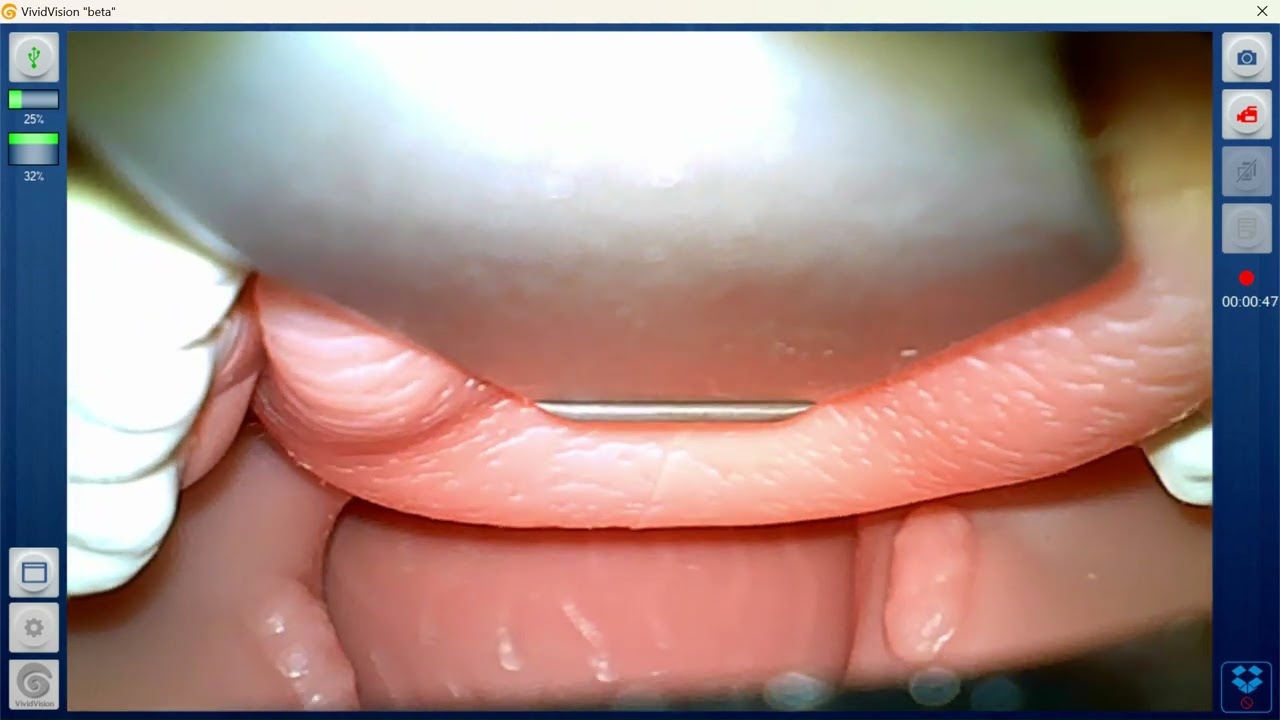

Review of the Laerdal Airway Management Trainer

Описание: This is an in-depth look at the Laerdal Airway Management Trainer. View product here: https://shop.vitalipartners.com/produ...